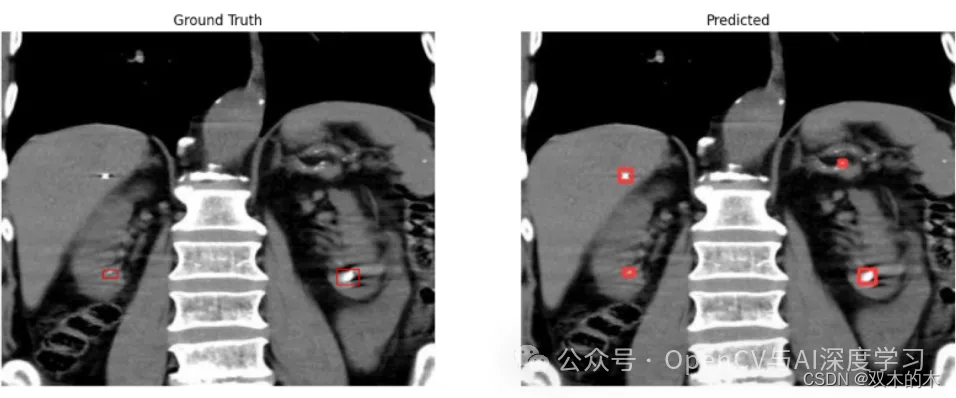

示例二:小肾结石(错检)

观察结果:另一方面,一些样本包含白色像素伪影,类似于较小的肾结石的外观。在这个样本中,可以观察到模型将白色像素伪影误认为是真正的结石。这是不可接受的,特别是在医学诊断中。